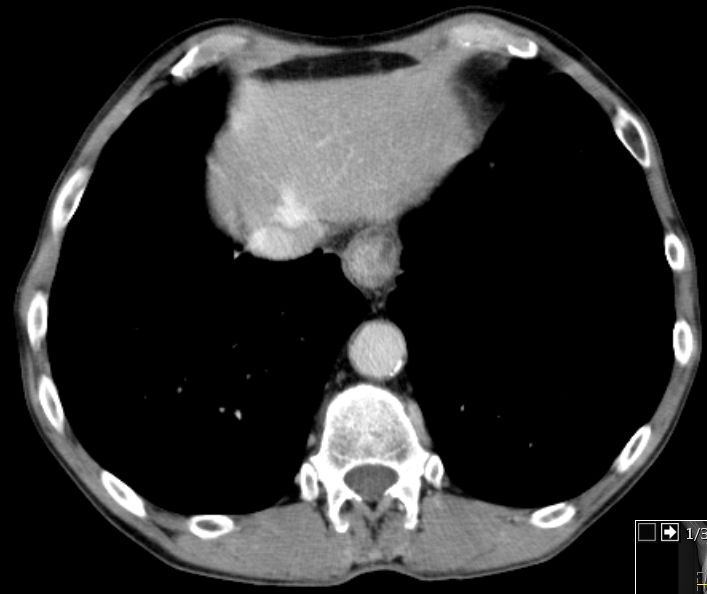

62-jähriger Mann mit schmerzhafter Schwellung des Sternums.

Die Stanzbiopsie ergab ein basaloides Plattenepithelkarzinom. Bei der Durchuntersuchung wurde ein asymptomatisches Ösophaguskarzinom gefunden.![]() |